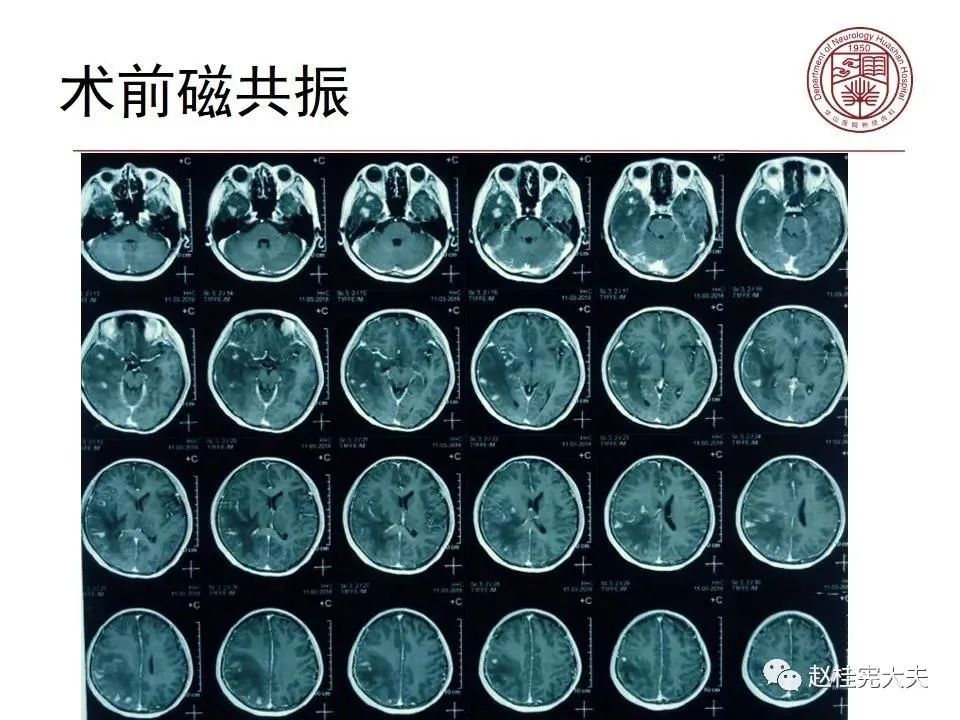

病例3